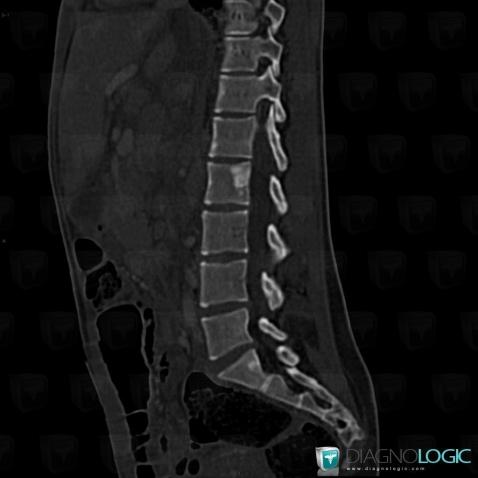

Sarcoïdose, Corps vertébral / Disque, Scanner

Voici les informations spécifiques à l'image clé ci dessus:

- Diagnostic Sarcoïdose, Localisation(s) Corps vertébral / Disque, comportant les gammes Condensation vertébrale focalisée